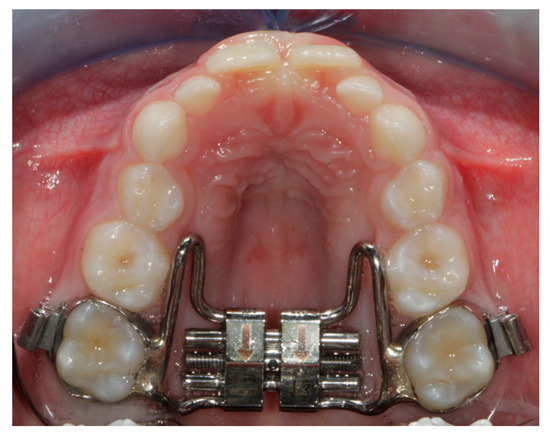

All the subjects of the study group (SG) underwent treatment with the Hyrax butterfly Rapid Maxillary Expander (RME) with Leone® screw with bands cemented on the upper permanent first molars (Figure 1).

Figure 1. Butterfly Rapid Maxillary Expander.